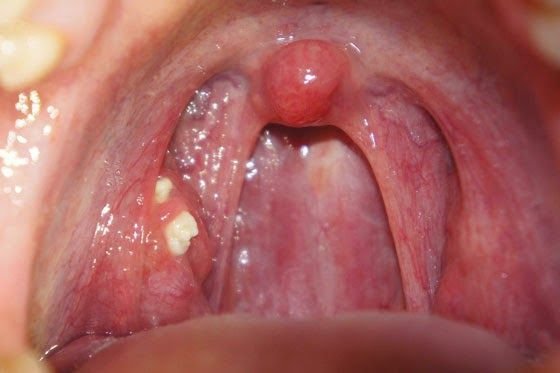

扁桃腺結石致口臭、喉嚨痛扁桃腺是喉嚨後兩側的腺體,充滿罅隙,當扁桃腺反覆發炎便會造成罅隙的小窩加深,食物殘渣或細菌容易卡在小窩中,2至3日之後與唾液及細菌混合,變成扁桃腺結石。結石會發出惡臭,令患者有口氣問題,甚至會喉嚨嚴重發炎,連吞嚥口水也痛。如果嚴重或致頭痛、耳朵痛癢、嘔吐等情形,建議直接去找耳鼻喉科醫生。

嚴重需開刀清除台灣媒體近日亦有就此進行報導。高雄長庚醫院耳鼻喉科主治醫師羅盛典表示,曾經某些患者有不只一顆結石,因患者扁桃腺位置的隱窩為「外窄內寬」構造,藏了多達10幾顆結石,需立即開刀摘除扁桃腺。另有耳鼻喉科專科醫生指,如果依網上流傳用牙籤或棉花自行剔走結石,有可能誤傷扁桃腺,導致反覆發炎,故建議患者先求診較好。